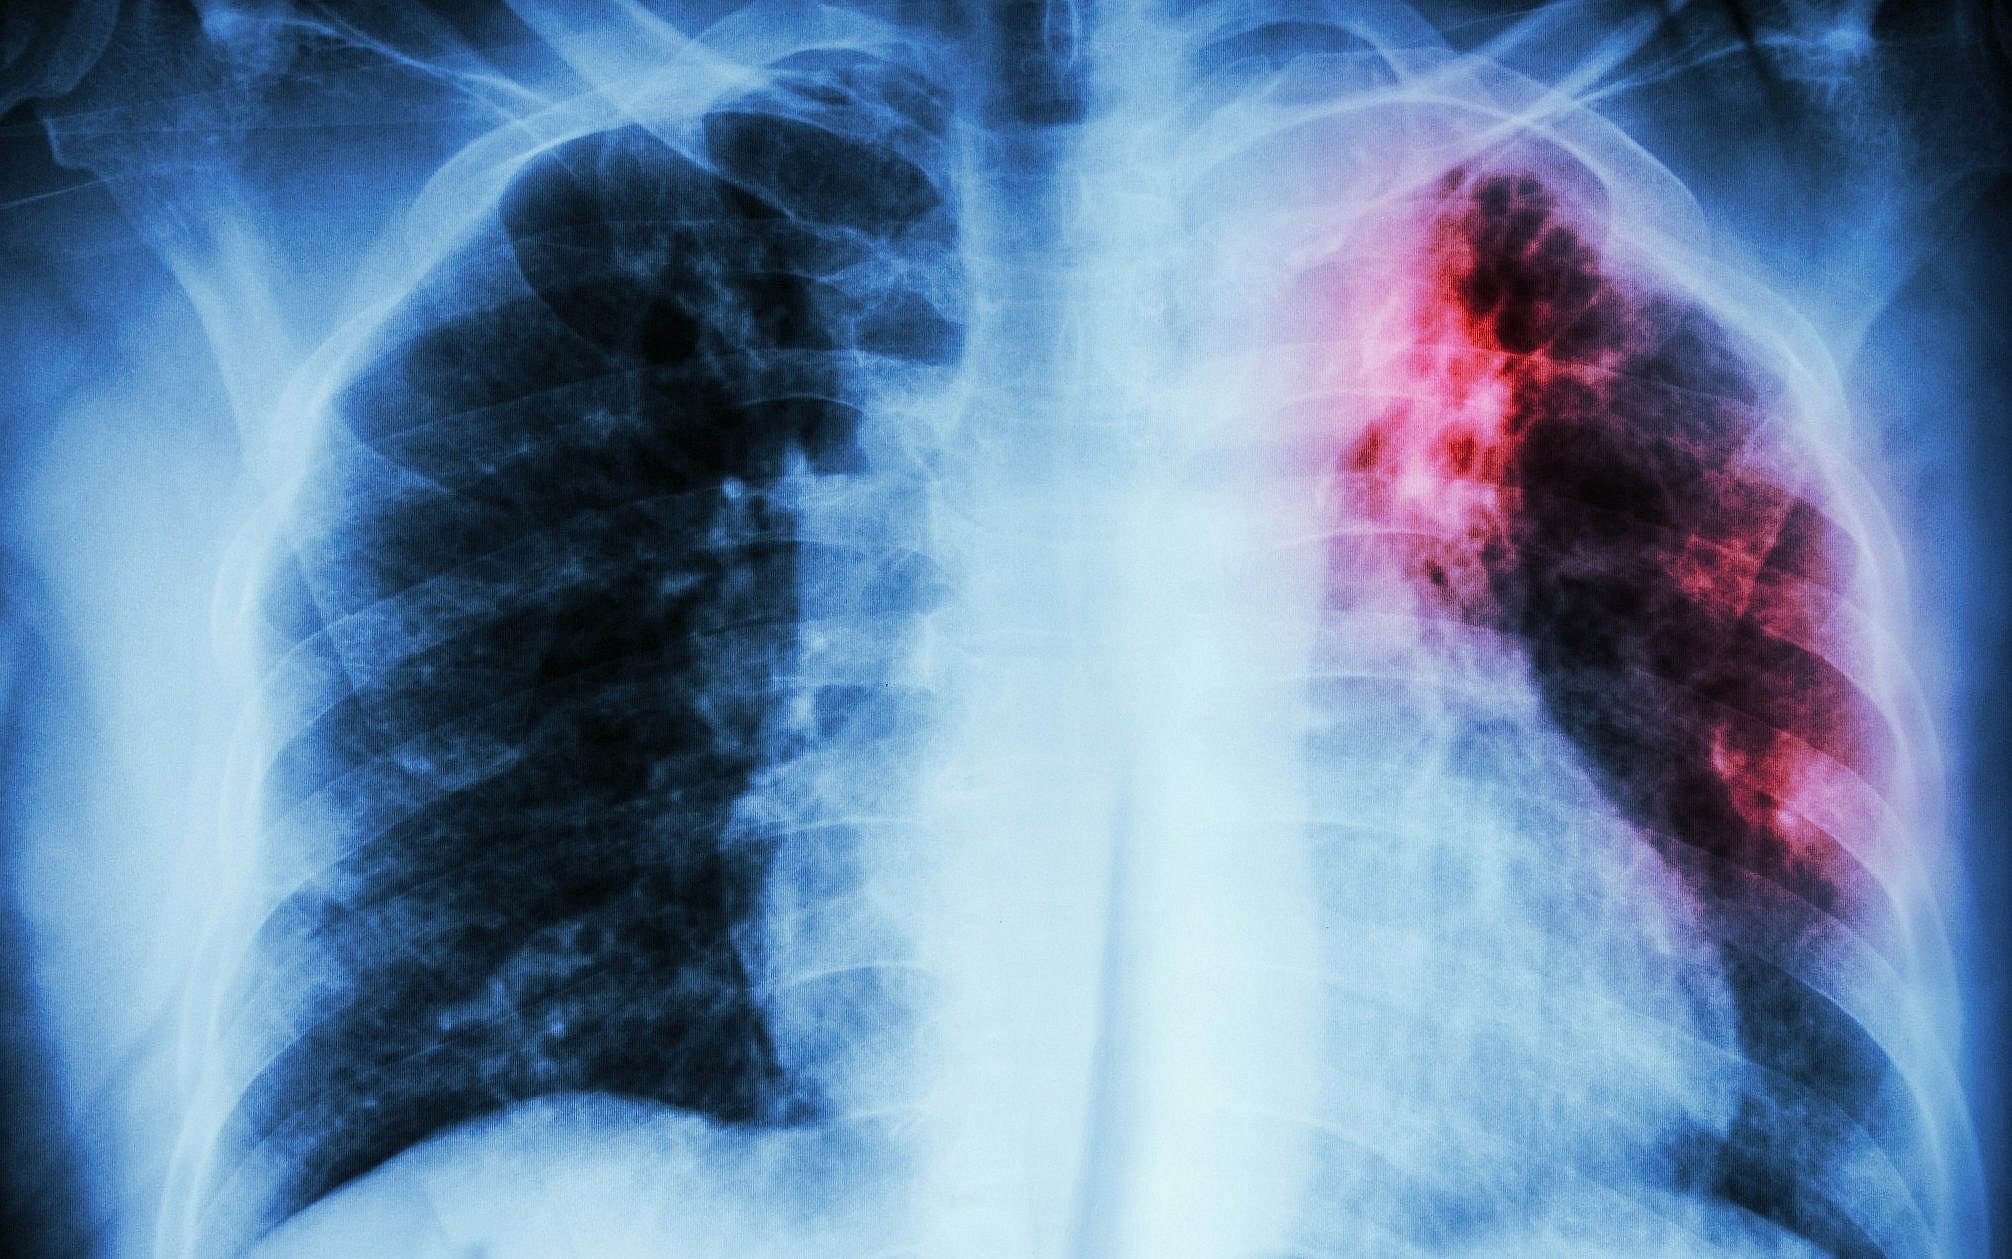

Пневмония - это серьезное заболевание легких, которое может быть вызвано различными причинами, включая бактериальные, вирусные и грибковые инфекции. Для того чтобы наглядно показать симптомы, диагностику и лечение этого заболевания, картинки могут быть очень полезны.

Картинки с симптомами пневмонии

В этом разделе представлены изображения, демонстрирующие различные симптомы пневмонии, такие как кашель, одышка, боль в груди и повышенная температура. Эти картинки могут быть использованы для обучения и презентаций в области медицины и здравоохранения.